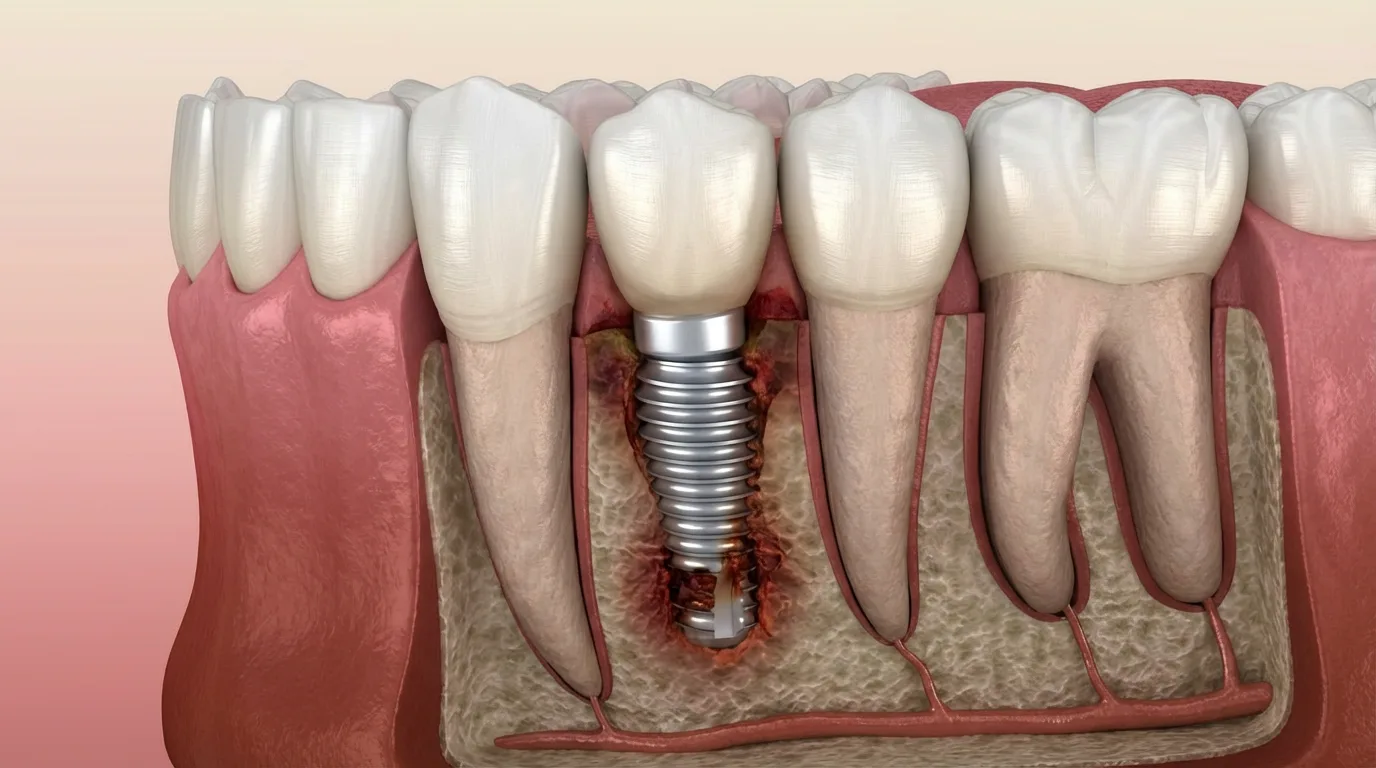

과거에 식립한 임플란트가 염증, 부착 실패, 파절 등으로 기능을 잃었을 때 손상된 부위를 정리하고 새로운 임플란트를 다시 식립하는 치료입니다.

재수술은 기존 뼈 상태가 좋지 않은 경우가 많아 더 정밀한 진단과 섬세한 접근이 필요합니다.

임플란트가 실패한 부위는 뼈가 약해져 있거나 염증 흔적이 남아있는 경우가 많습니다. 따라서 재수술은 단순히 다시 심는 것이 아니라 원인을 정확히 찾고, 구조를 회복시키며, 다시 안정적인 상태로 만드는 과정이어야 합니다.